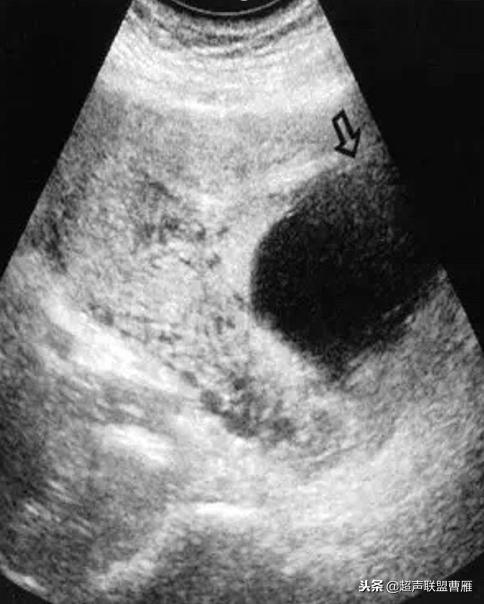

Ⅱ型孕囊胚胎停育型

1.子宫下段见变形妊娠囊,无胎心搏动,见扩张血管及多量血池

2.孕囊周围局部肌层血流信号丰富,可记录到类滋养层周围血流频谱

(Ⅱ型孕囊胚胎停育型)